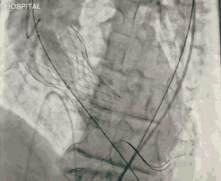

今天直播的这位患者是85岁的老年男性,10年前因主动脉瓣重度狭窄植入CoreValve 26mm瓣膜,是我国第一例TAVR患者,术后恢复情况良好。

葛均波院士、周达新教授结构团队对这位生物瓣衰败的老年男性患者行瓣中瓣植入术,术中选择了23mm VenusA-Valve(杭州启明),植入过程顺利,术后冠脉无堵塞,未出现瓣周漏,术后跨瓣压差接近于0,赢得了参会专家的激烈掌声。

图3 TAVR瓣膜释放前造影

图4 TAVR球囊前扩张

图5 TAVR瓣膜释放后